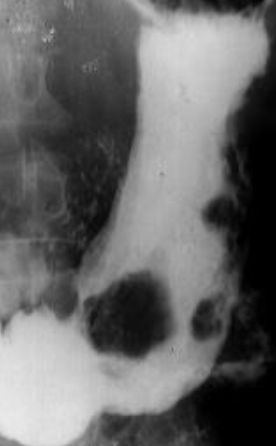

Neoplasm malign gastric vegetant